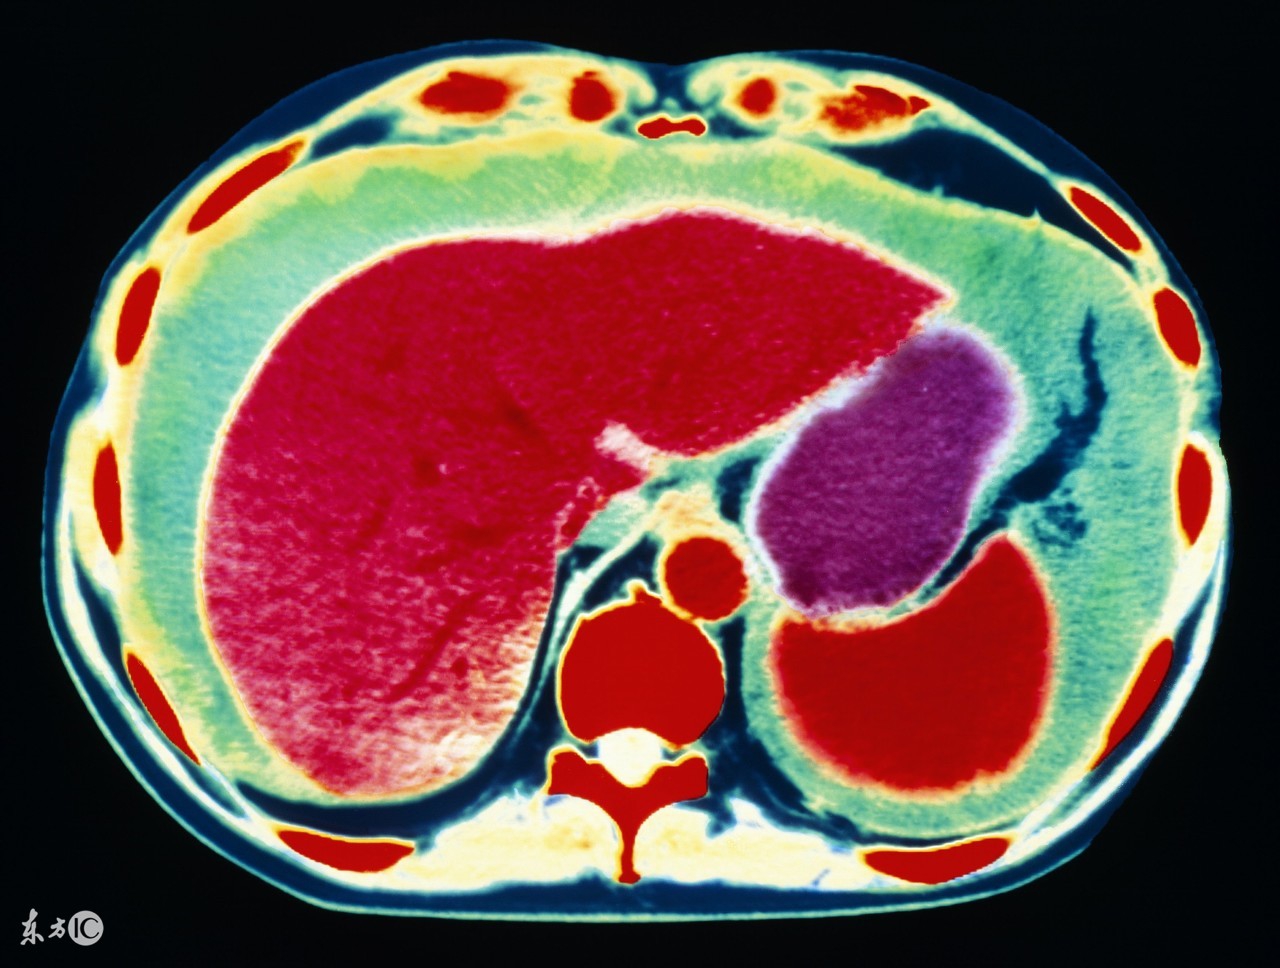

1、肝癌。前面说了,肝病是引起腹水最常见的原因,其中肝癌就是其一。原发性肝癌,发展到一定程度,合并腹水的可能性非常大,其实本质上仍是肝硬化所致,所以肝腹水就是肝硬化腹水。肝硬化时,肝细胞变性、坏死、纤维组织增生,肝内血管床受压、扭曲、变形、狭窄,阻塞了血管,使肝窦淤血,血流量大大降低,门静脉压力升高,同时,毛细血管静脉压力也升高,久而久之,胃肠道、肠系膜、腹膜等血液回流受阻,血管通透性升高,血液中的血浆成分外漏,形成了腹水。肝功能不合,肝脏不能合成白蛋白,低蛋白血症,由于血清白蛋白的降低,血管内胶体渗透压下降,血浆成分外渗而形成腹水。所以,不管什么肝病,到了肝硬化,肝功能不全的阶段,就可能形成腹水。

3、卵巢癌,包括输卵管癌、原发性腹膜癌,这三种癌症的治疗原则是一样的,这类癌症也是引起腹水的最常见原因之一,女性如果有大量的腹水,要首先排除卵巢癌可能,有针对性的重点查一查卵巢输卵管。